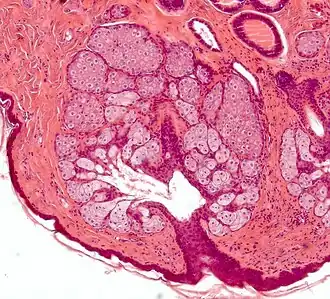

- glande acineuse : en forme de grain de raisin (akinos : graine de raisin) toujours avec un canal excréteur, simple ou composé ;

- les glandes holocrines : la cellule entièrement chargée de substance se détache de l'épithélium et se désintègre au moment de la sécrétion. Exemple : glande sébacée ;